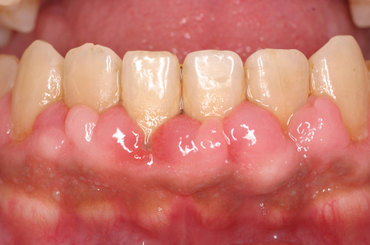

C.は、例えば緑内障などの目の病気、副鼻腔炎(蓄膿)などの鼻の病気、中耳炎などの耳の病気、虫歯や歯槽膿漏などの口腔内の病気、あるいは三叉神経痛(一般の方はよく顔面神経痛などと言いますが、本来顔面神経は顔面の表情筋を動かす運動神経なので痛みを感じる神経ではありません)などによる頭痛とか顔面痛です。